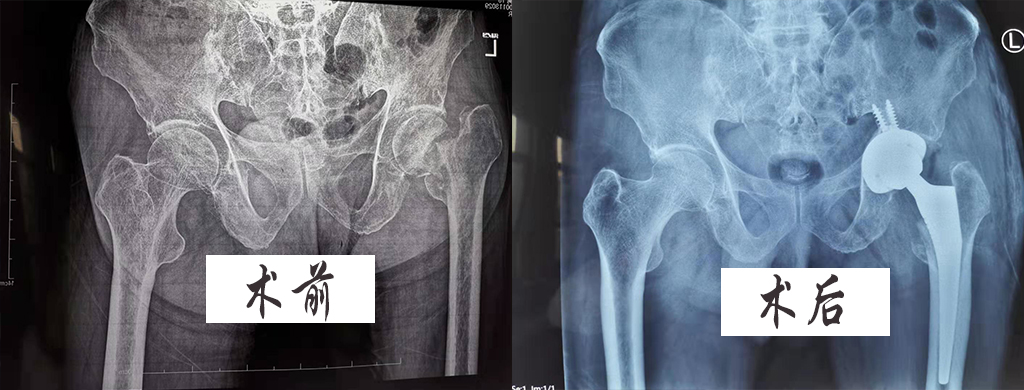

原來患者曾先生,在年初旅游時不慎摔傷左髖部,據(jù)家屬介紹:在當(dāng)?shù)蒯t(yī)院X線片檢查后為“左股骨頸骨折”,當(dāng)時并未住院治療,僅在家保守治療,期間未看到明顯好轉(zhuǎn),再后來X線片檢查“左股骨頸陳舊性骨折,未愈合,下肢明顯短縮”,并伴有夜間疼痛,一直臥床不能行走等情況。

在經(jīng)過專業(yè)詳細(xì)的體格檢查、??茩z查、輔助檢查后,初步診斷為“1、左股骨頸陳舊性骨折2、左側(cè)股骨頭壞死3、類風(fēng)濕性關(guān)節(jié)炎”情況,在完善檢查排除手術(shù)禁忌后,準(zhǔn)備給予“做人工股骨頭置換術(shù)+髖關(guān)節(jié)滑膜切除術(shù)”。

在征得家屬同意后,于2019年11月21日在麻醉科的會診下進(jìn)行了手術(shù),術(shù)中術(shù)后順利,期間又給予了預(yù)防感染、消腫、抗凝等治療,曾先生于術(shù)后三日就可以在家人的協(xié)助下行走,家屬非常滿意,直到出院時曾先生一般情況,飲食、睡眠、大小便均正常,恢復(fù)較好。